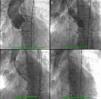

A 26-mm aortic valve prosthesis (Medtronic CoreValve™) was implanted using a transfemoral approach, with an excellent final angiographic result (Figure 2). The procedure was performed under general anesthesia and VMI following elective orotracheal intubation, guided by bronchofiberscopy due to the patient's facial deformities and problematic airway. Weaning from ventilatory support was rapid, with extubation within 24 hours. A setting of type 2 respiratory failure and fever began on the first postoperative day; non-invasive ventilation with BiPAP was instituted and blood samples collected for testing, which was negative. A chest X-ray revealed infiltrate in the left lung base and widespread nodular lesions in cervical and thoracic soft tissues, associated with lipodystrophy. Empirical antibiotic therapy was begun with levofloxacin. Laboratory tests showed leukocytosis (27.7×109/l) with neutrophilia and C-reactive protein of 10.4 mg/dl.

Transthoracic echocardiography showed the aortic prosthesis to be correctly positioned, with a peak transvalvular gradient of 17 mmHg, a small central regurgitant jet, and preserved left ventricular systolic function (Figure 3).